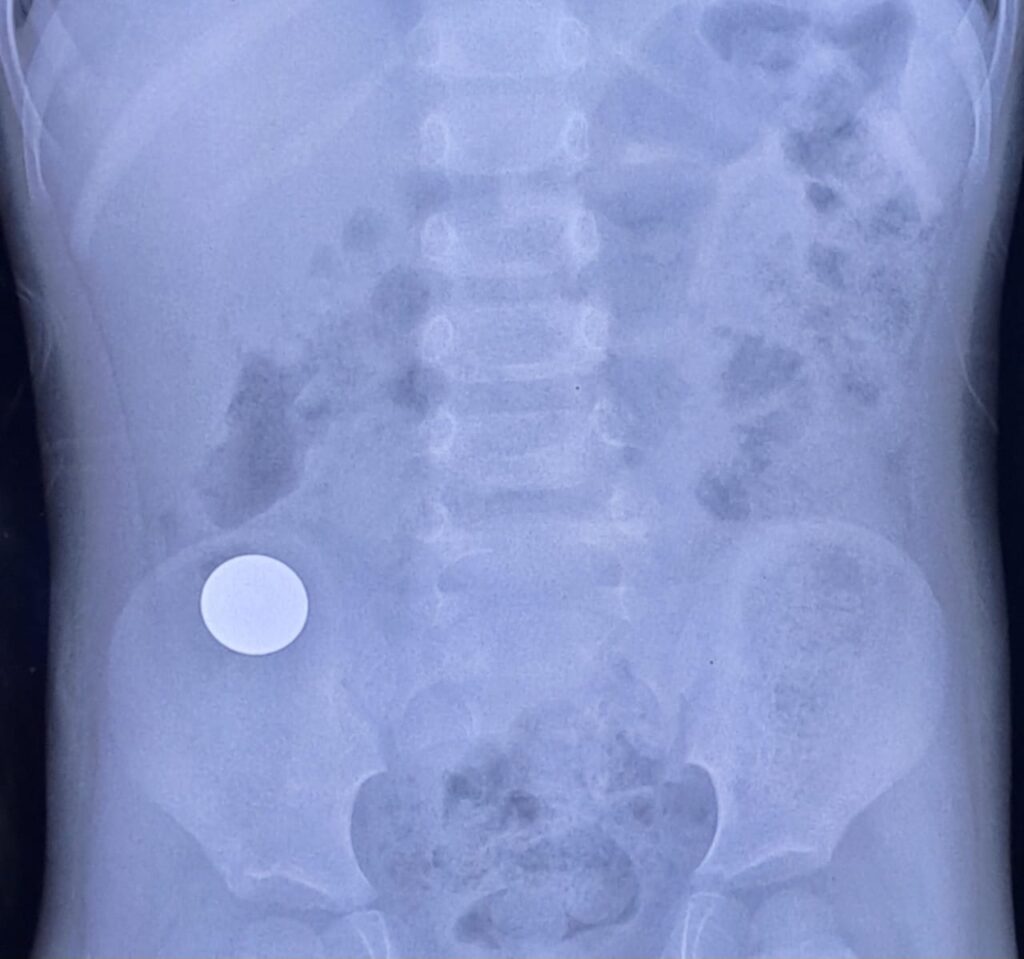

Accidental coin ingestion. Asymptomatic.

Round metallic density projected over right iliac fossa in keeping with a coin. No features of bowel obstruction.

Observation is required for passage of coin in stool.